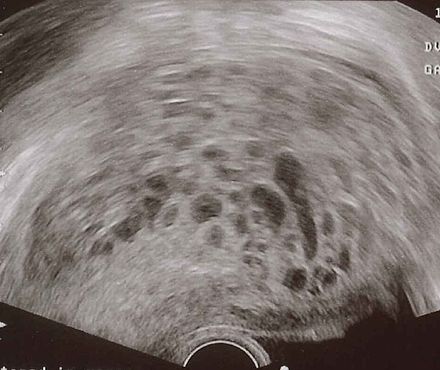

Извънматочната бременност

Публикувано на: 09.01.2007 Извънматочната бременност – това е състояние, при което оплодената яйцеклетка се прикрепва и започва...

ПовечеЕктопичната бременност

Публикувано на: 09.01.2007 "Ектопичната бременност (ЕБ) е описана за първи път от Riolan (1626 год.), но и до днес създава сери...

ПовечеИзвънматочната бременност

Публикувано на: 05.11.2003 Това е бременност, при която оплодената яйцеклетка вместо да премине през една от фалопиевите тръби ...